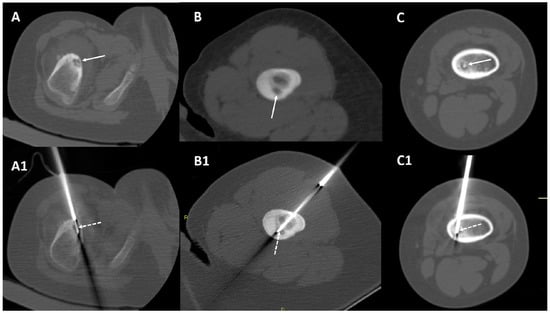

2.2. CT-Guided Radiofrequency Ablation

| 35 | 42 | Continuous pain worsened at night | Tibia diaphysis, cortical-periosteal | 12 mm | 15 mm | Yes | Yes | Osteoid osteoma | 4 months after treatment: asymptomatic | 7 years after treatment: asymptomatic |